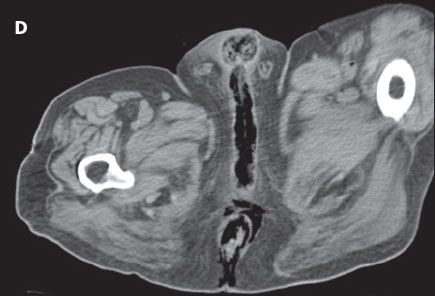

CT scans of the abdomen and pelvis showed a large prostatic mass without delineation between the prostate, rectum, and bladder. A fistula was noted between the rectum and bladder (A, B, and C). Copious subcutaneous gas was visible in the perineum and in all 3 corpora of the penis (D). Blood cultures were positive for Clostridium perfringens. Necrotizing fasciitis was diagnosed, and the patient underwent a loop colostomy.